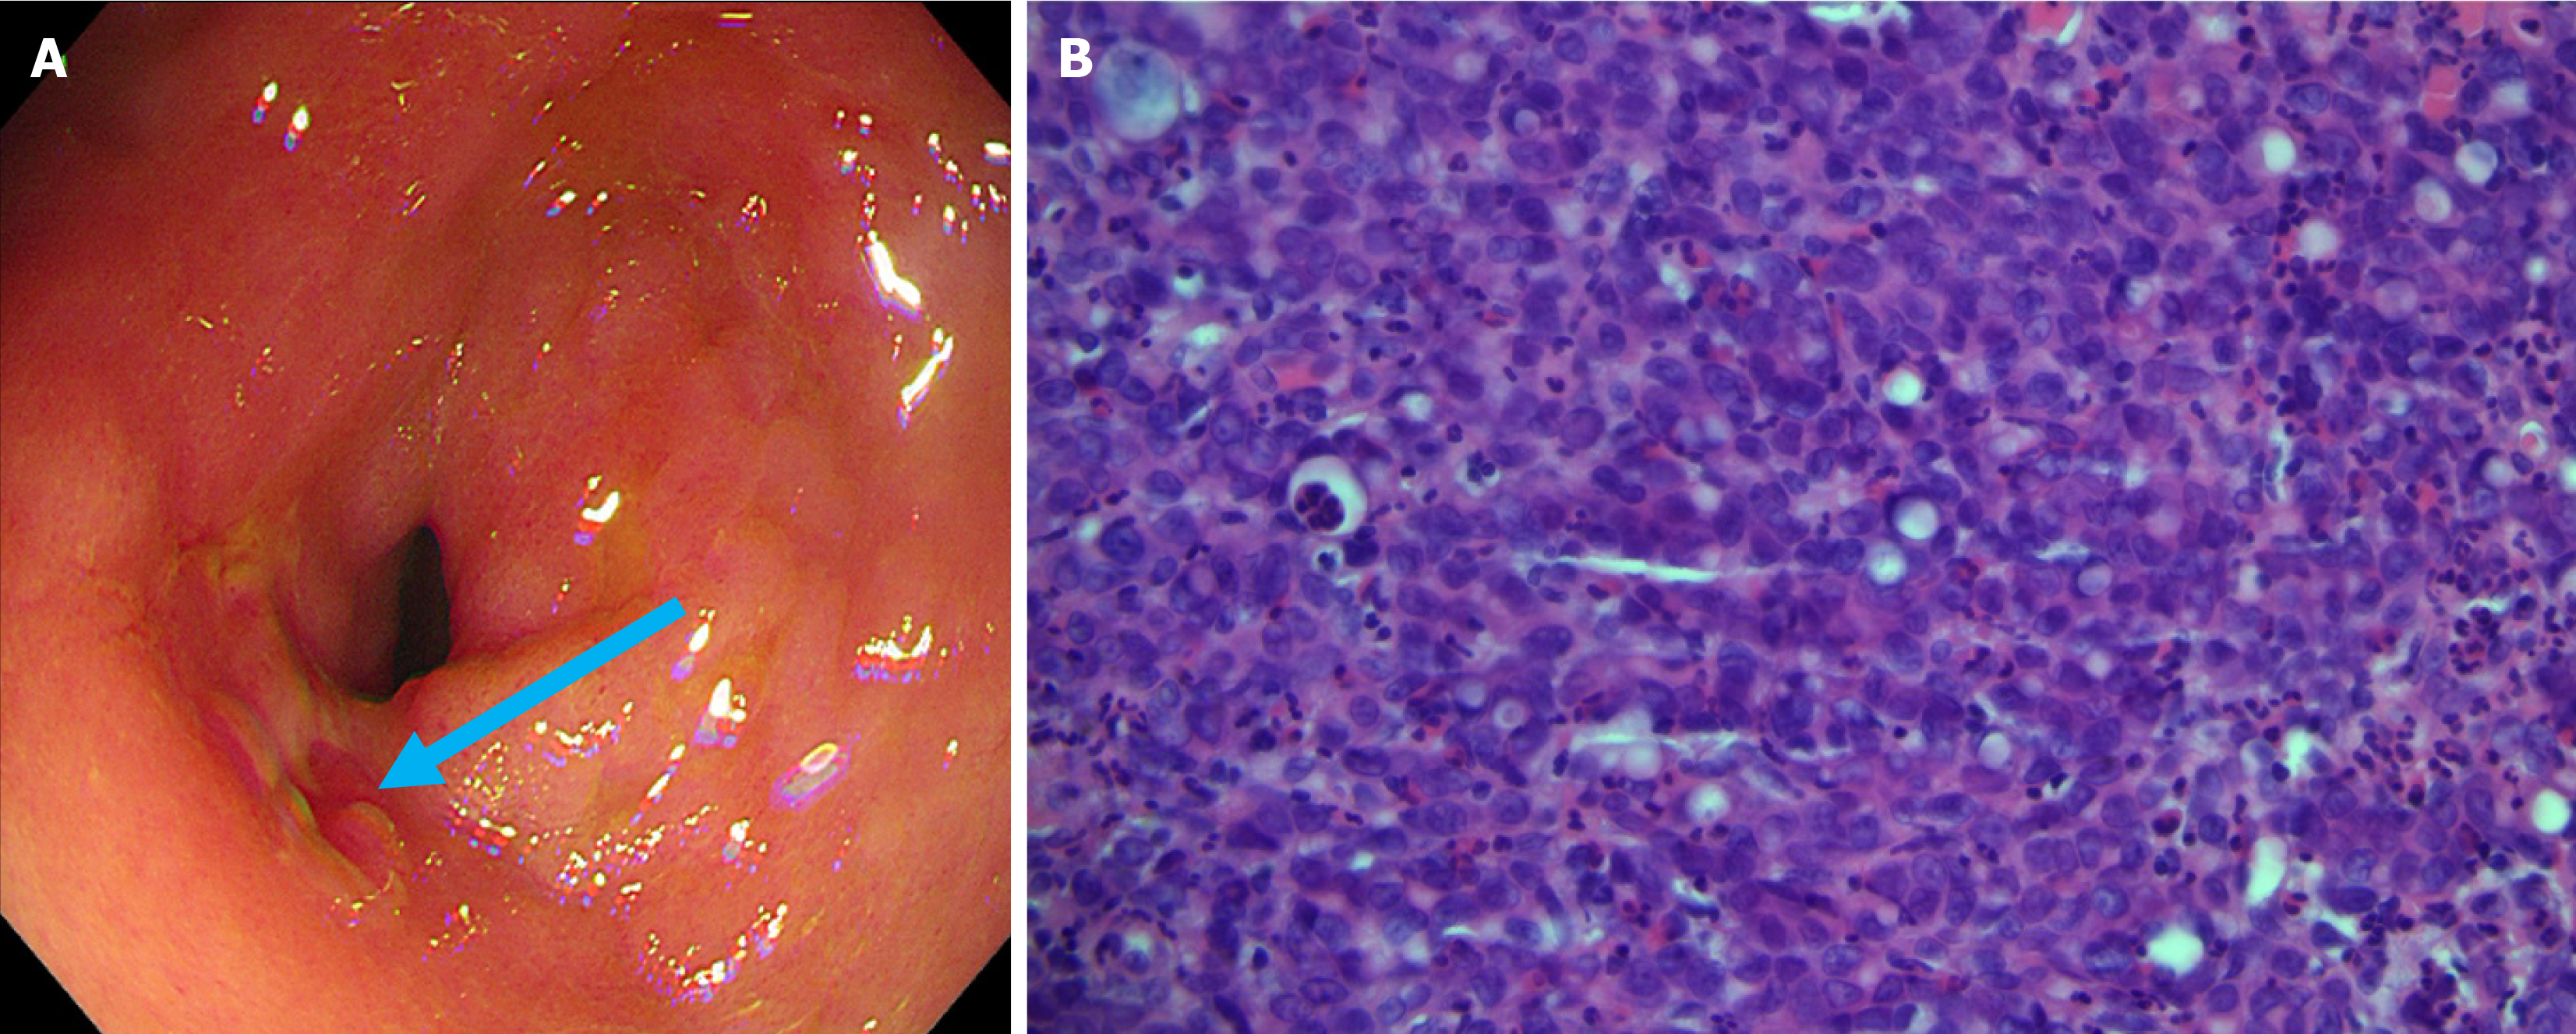

Figure 4 Patient’s gastroscopy and pathology images.

A: Gastric antral mucosa with scattered erythematous erosions, and a 1.0 cm erosion in the prepyloric area (blue arrow); B: Pathology showed the gastric antrum lesion to be consistent with poorly differentiated adenocarcinoma (hematoxylin and eosin 400 ×).